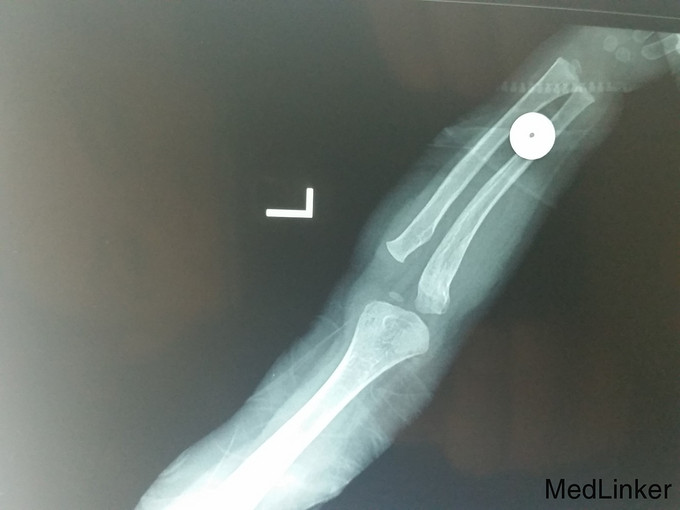

复杂骨折

骨折

男,1岁10月,约1米高台跳下时伤及左侧肘部,肿胀活动受限

左上肢石膏长臂石膏后托固定,左手活动可

请教各位诊断及治疗方案